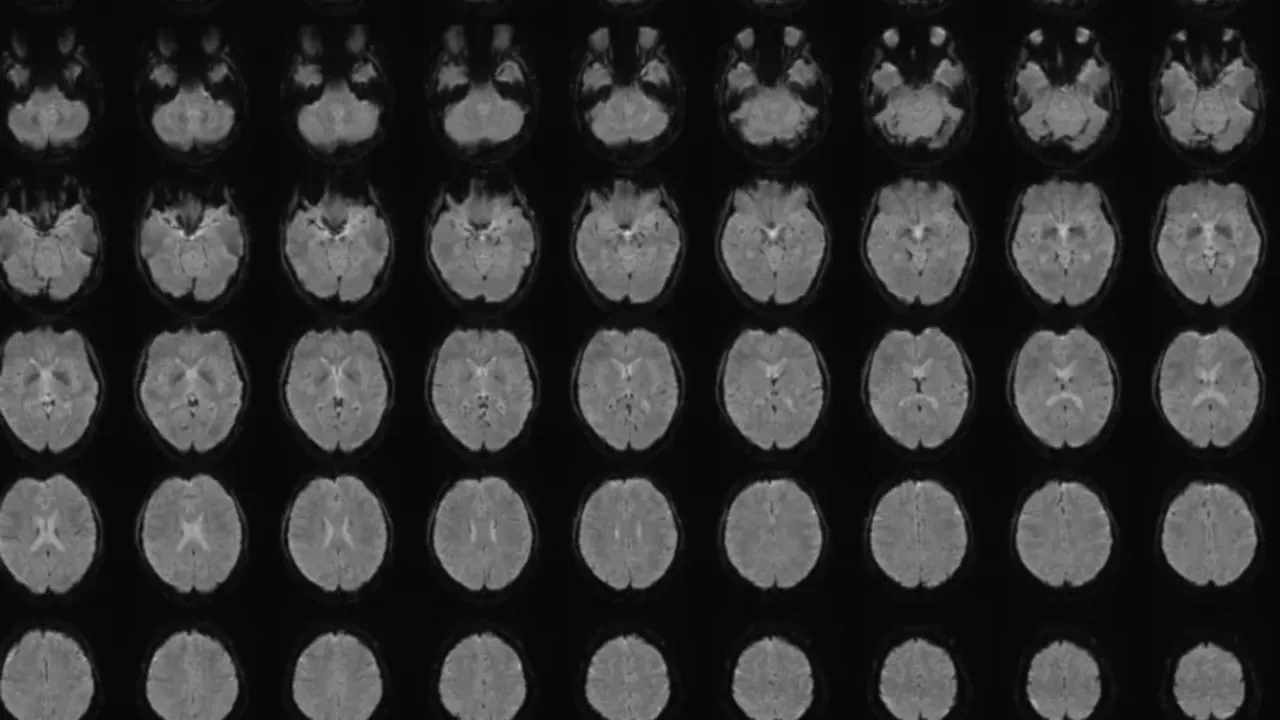

Japonya’da bir bilim insanı, beyin taramaları ve yapay zekâ kullanarak kişinin zihnindeki görüntüleri doğru ve açıklayıcı cümlelere dönüştürebilen bir teknik geliştirdi.

Araştırmada 22-37 yaşları arasındaki 6 Japon katılımcının beyin aktiviteleri, 2180 sessiz video klip izlerken tarandı. Büyük dil modelleri (LLM), videolara ait altyazıları sayısal dizilere dönüştürdü ve ardından “çözücüler” (decoders) olarak adlandırılan yapay zekâ modelleri, beyin aktiviteleri ile bu dizileri eşleyecek şekilde eğitildi.